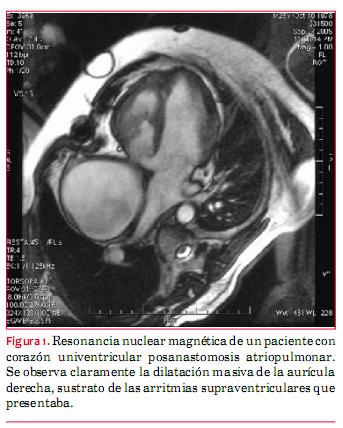

· Hay un segundo grupo de causas adquiridas y que son las que devienen de los tratamientos invasivos recibidos (figura 1). Se originan por el traumatismo directo de los tejidos, por ejemplo incisiones, interposiciones de materiales como los parches de pericardio, cierre de orificios con dispositivos, abocamiento de vasos/tubos, etcétera. Los trastornos del ritmo son más frecuentes en los pacientes con CC que han sido sometidos a algún procedimiento. Se lo acepta como un costo a pagar. Cuanto más tarde se realiza el procedimiento, correctivo o paliativo, mayor el riesgo de tener arritmias en el futuro.

El desarrollo de arritmias en adultos con CC debe considerarse como un “mensajero” de alteraciones en el estado hemodinámico. Ante la detección de una arritmia se debe evaluar de manera minuciosa esta situación. Se debe solicitar la realización de un ecocardiograma por personal capacitado en CC. La resonancia magnética está adquiriendo un lugar cada vez más importante en el mundo.